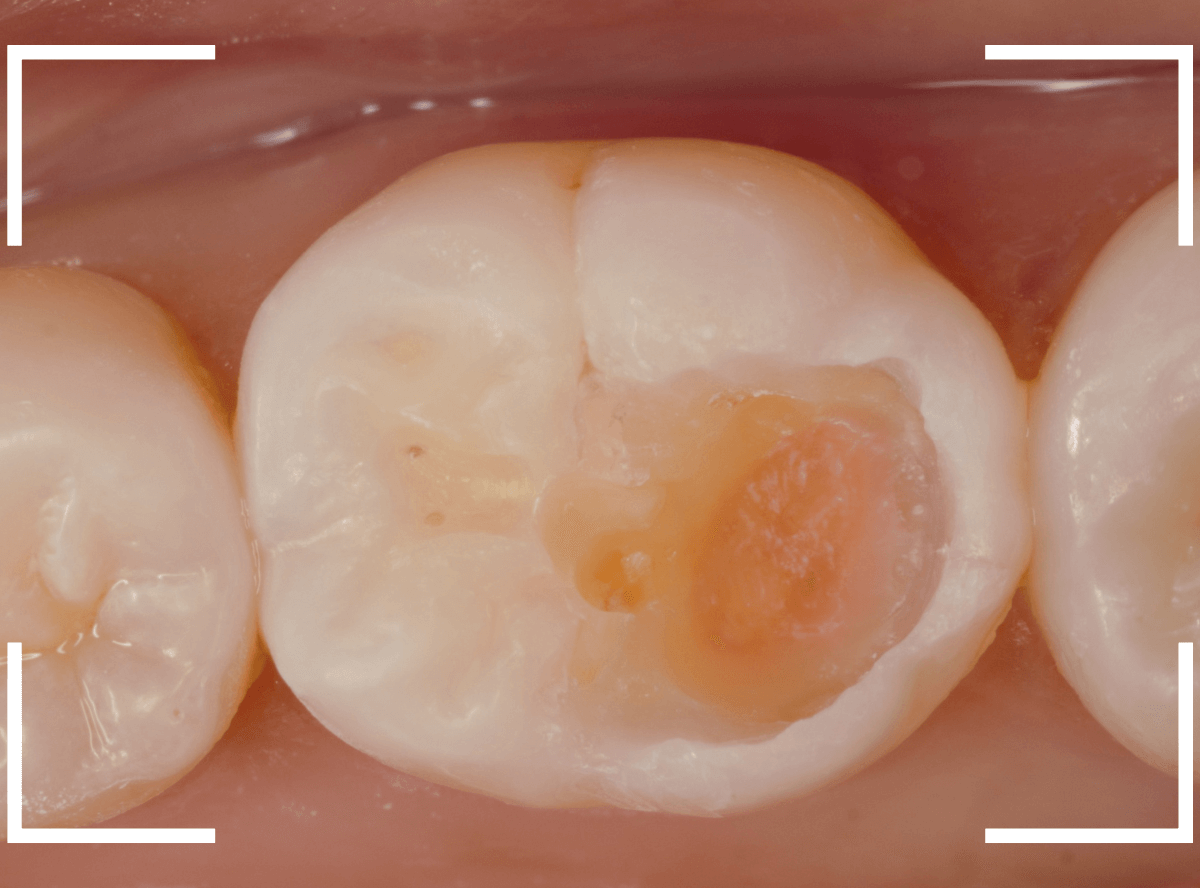

Case.17 レントゲンにはっきり写らないレジンの中の虫歯を削って調べる2

今回も、下の奥歯の虫歯を治療した例です。

特に症状はありませんが、以前に治療したレジンが劣化してすり減っているのと、少し中が黒く透けて見えて、虫歯になっているのが怪しいです。

青いラインが歯の神経です。

以前の虫歯が深めだったようで、レジンが深めにつめてあるのがわかります。

その下がうっすらと虫歯っぽい影になっています(赤いライン)。

虫歯になっているか微妙なラインですが、レジンも劣化していますので、患者さんにご説明して治療することになりました。

レントゲンで虫歯と思われる部分をレジンを除去しました。

見た目には虫歯かどうかはっきりわかりません。

う蝕検知液で染め出します。

うっすらと赤く染色されました。

レントゲン写真と同じく、レジンの下で静かに虫歯が進行し始めていたようです。

もともと深めの虫歯だった部分なので、早いうちに治療が進められてよかったです。

全てのレジンと虫歯を除去しました。

お薬をつめて、症状が出ないかしばらく経過観察します。

歯の外壁部分も薄くなってますので、レジンでは長期保存は難しいと思われます。

今回は、インレーで最終修復する予定です。